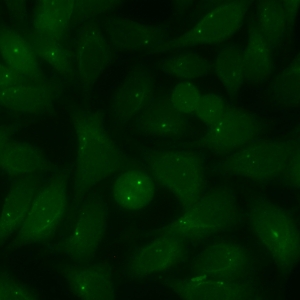

AC-24 - Centrosome

Previous Nomenclature Centrioles

Description Distinct centrosomes/centrioles (1-2/cell) in cytoplasm and at the poles of mitotic spindle